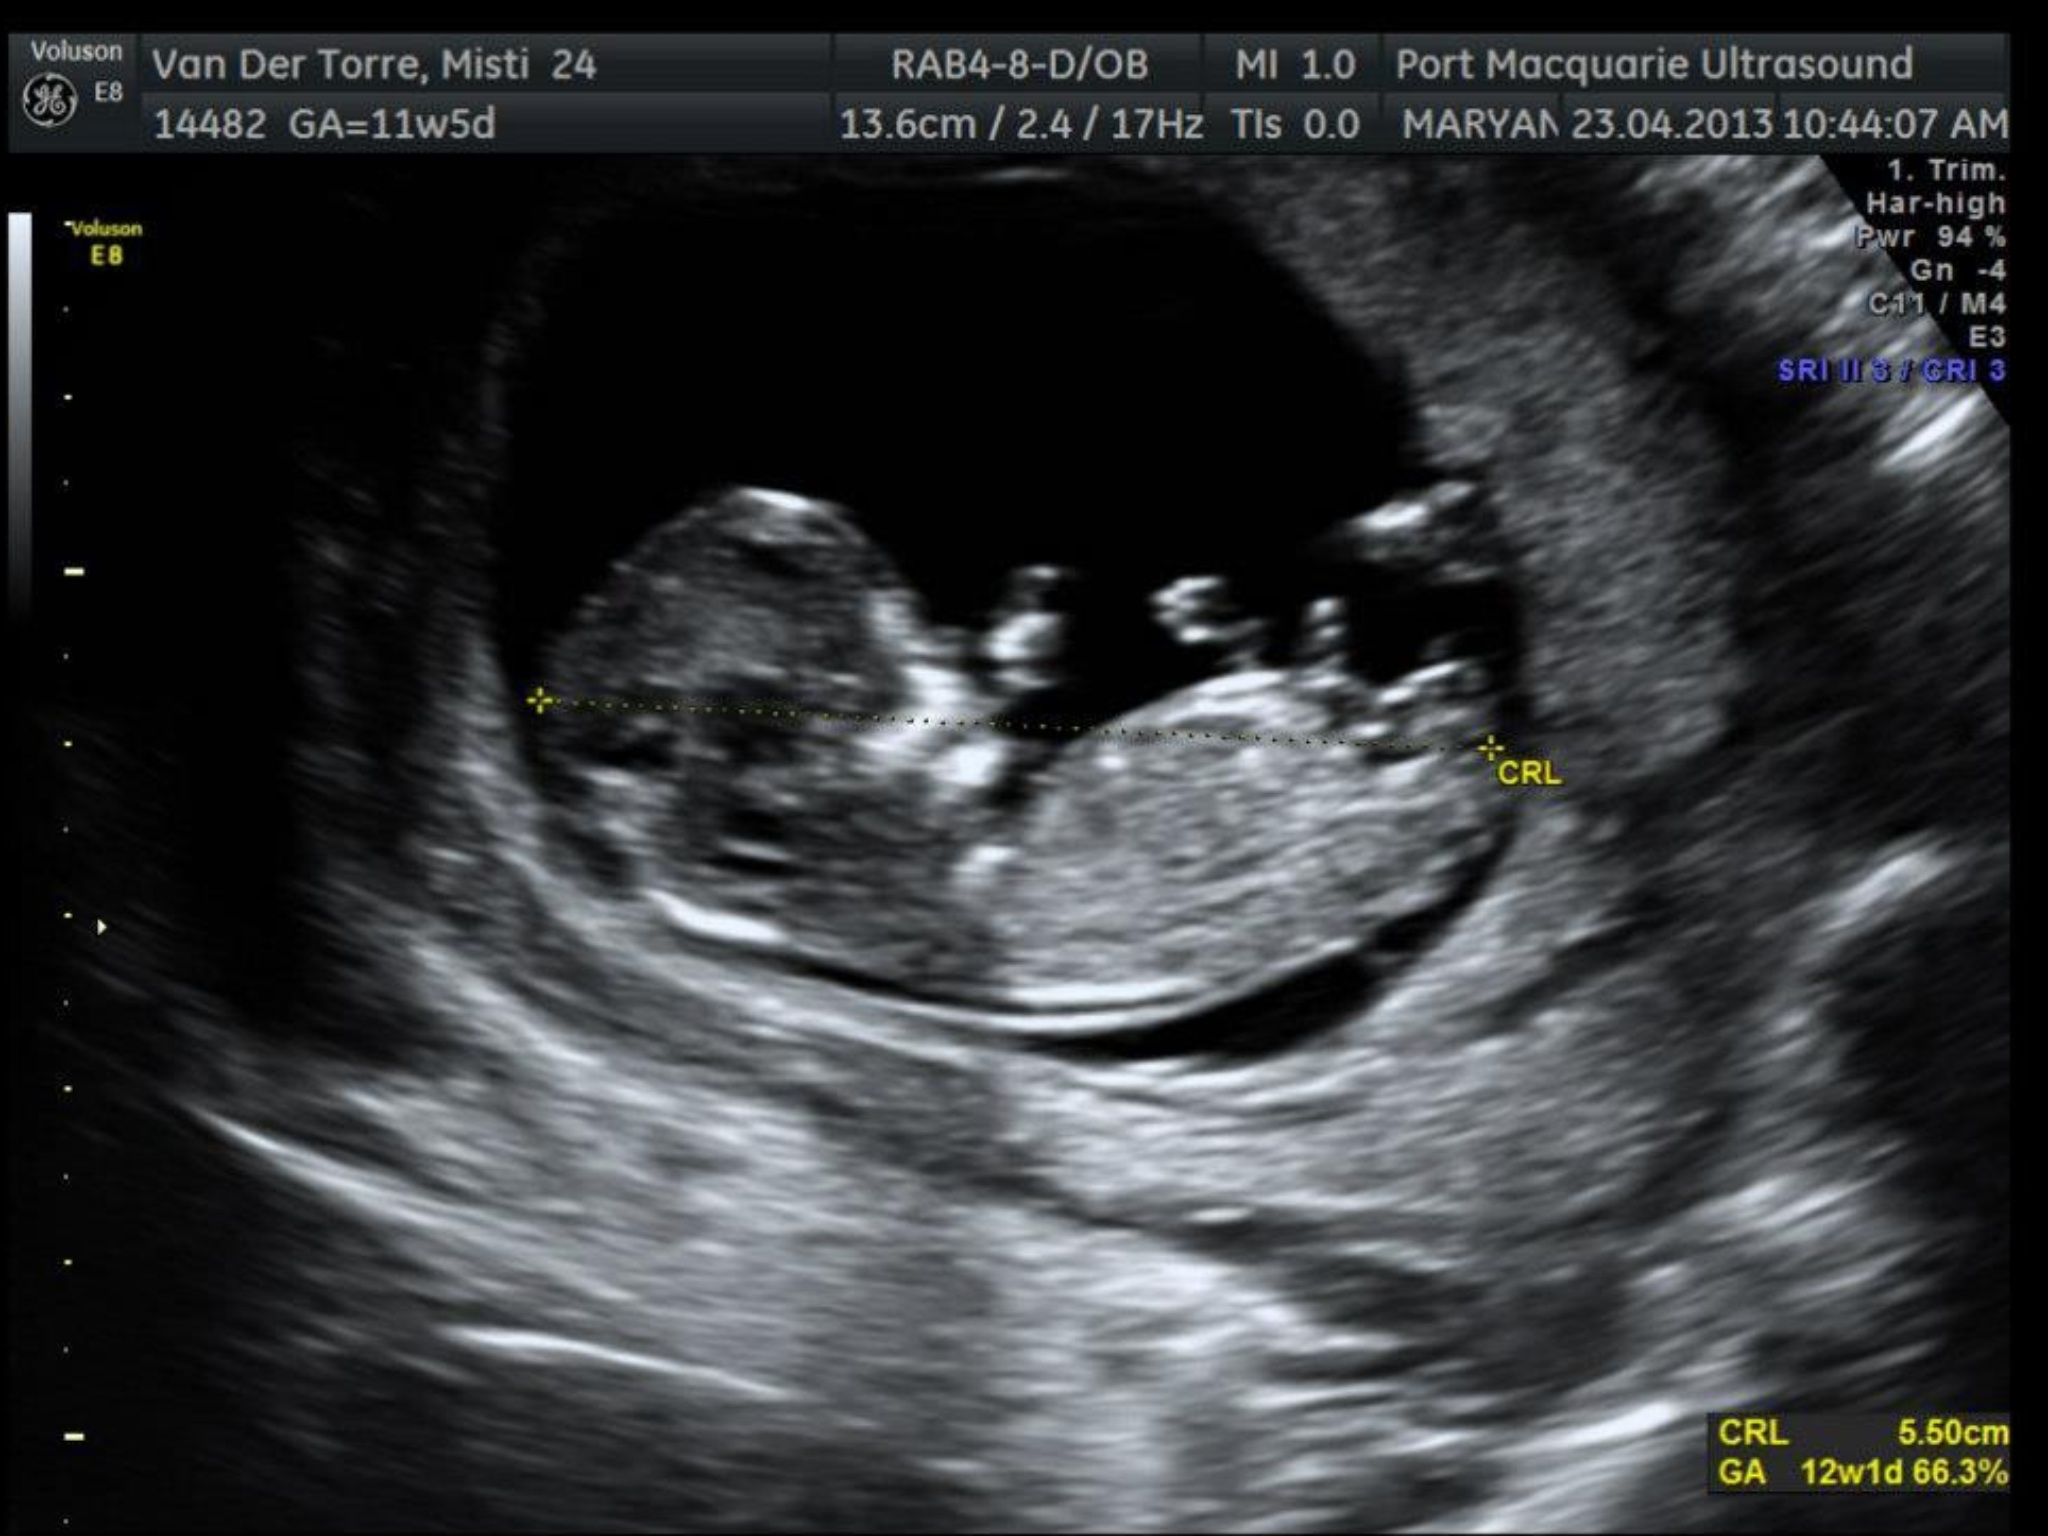

Hi all! I'm new here, just had my 12 week scan yesterday. I think I got 1 nub shot but there were 3 potentials. If anyone is willing to give their thoughts it would be greatly appreciated!

still too early at 11 weeks 5 days so i would say 50/50

It's too early to say for sure. Looks girly to me at the moment but there's only a 50/50 chance of it staying that way.

I would girl at current gestation. But could rise.